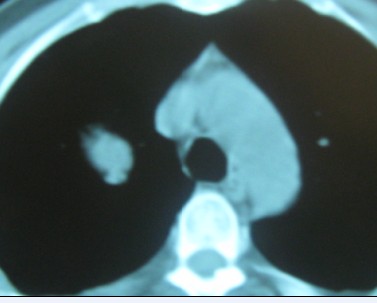

标题: CT192450:男37,自觉胸闷两月余 [打印本页]

标题: CT192450:男37,自觉胸闷两月余

考虑动脉瘤

右肺上叶良性肿瘤---错构瘤/硬化性血管瘤/炎性假瘤等。

考虑血管源性肿瘤,硬化性血管瘤可能性大;

不除外错构瘤。

考虑右肺上叶良性肿瘤(硬化性血管瘤?炎性假瘤?)。

边缘有毛刺,考虑癌